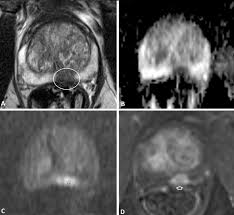

Diagnosis Of Transition Zone Prostate Cancer By Multiparametric Mri Added Value Of Mr Spectroscopic Imaging With Slaser Volume Selection Journal Of Biomedical Science Full Text

Diagnosis Of Transition Zone Prostate Cancer By Multiparametric Mri Added Value Of Mr Spectroscopic Imaging With Slaser Volume Selection Journal Of Biomedical Science Full Text from media.springernature.com